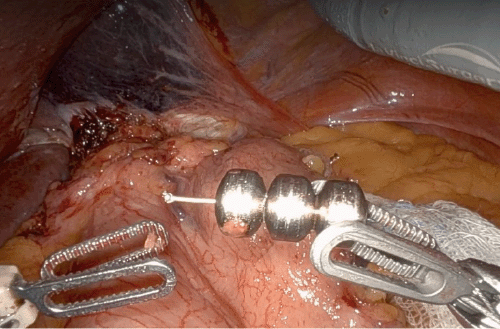

We performed a robotic hiatal hernia repair, MSAD removal, and Toupet fundoplication on an elective basis. A Toupet wrap was selected based on the patient's presenting symptoms of dysphagia, delayed passage of barium tablet on esophagram, and weak esophageal contractility on HRM. Dense inflammation was noted around the diaphragmatic hiatus on entry into the abdomen. Initially, we transected the gastrohepatic ligament up to the right crus and completely divided the phrenoesophageal ligament along the edges of the hiatus. During lateral dissection, we noticed a disruption of the LINX at the titanium link between two beads, which confirmed that it was not the clasp of the LINX. Inadvertently, during medial dissection, we broke the titanium wire in another region, three beads down from the initial disruption. Subsequently, posterior dissection to the esophagus created a retro-esophageal window where we found the remaining three beads with wire disruptions on the terminal ends. We brought the fundus posteriorly to form our Toupet wrap using the window created to find the beads. The device was removed in two pieces, and after reviewing preoperative imaging and previous operative reports, we confirmed removal of all beads. She had an unremarkable postoperative course and reported immediate resolution of her dysphagia. At her three-month follow-up, she continued to experience relief of her symptoms.

Figure 2. Discontinuity of Titanium Wire and Beads, A) Medial and B) Lateral Portions. Published with Permission

A.

B.